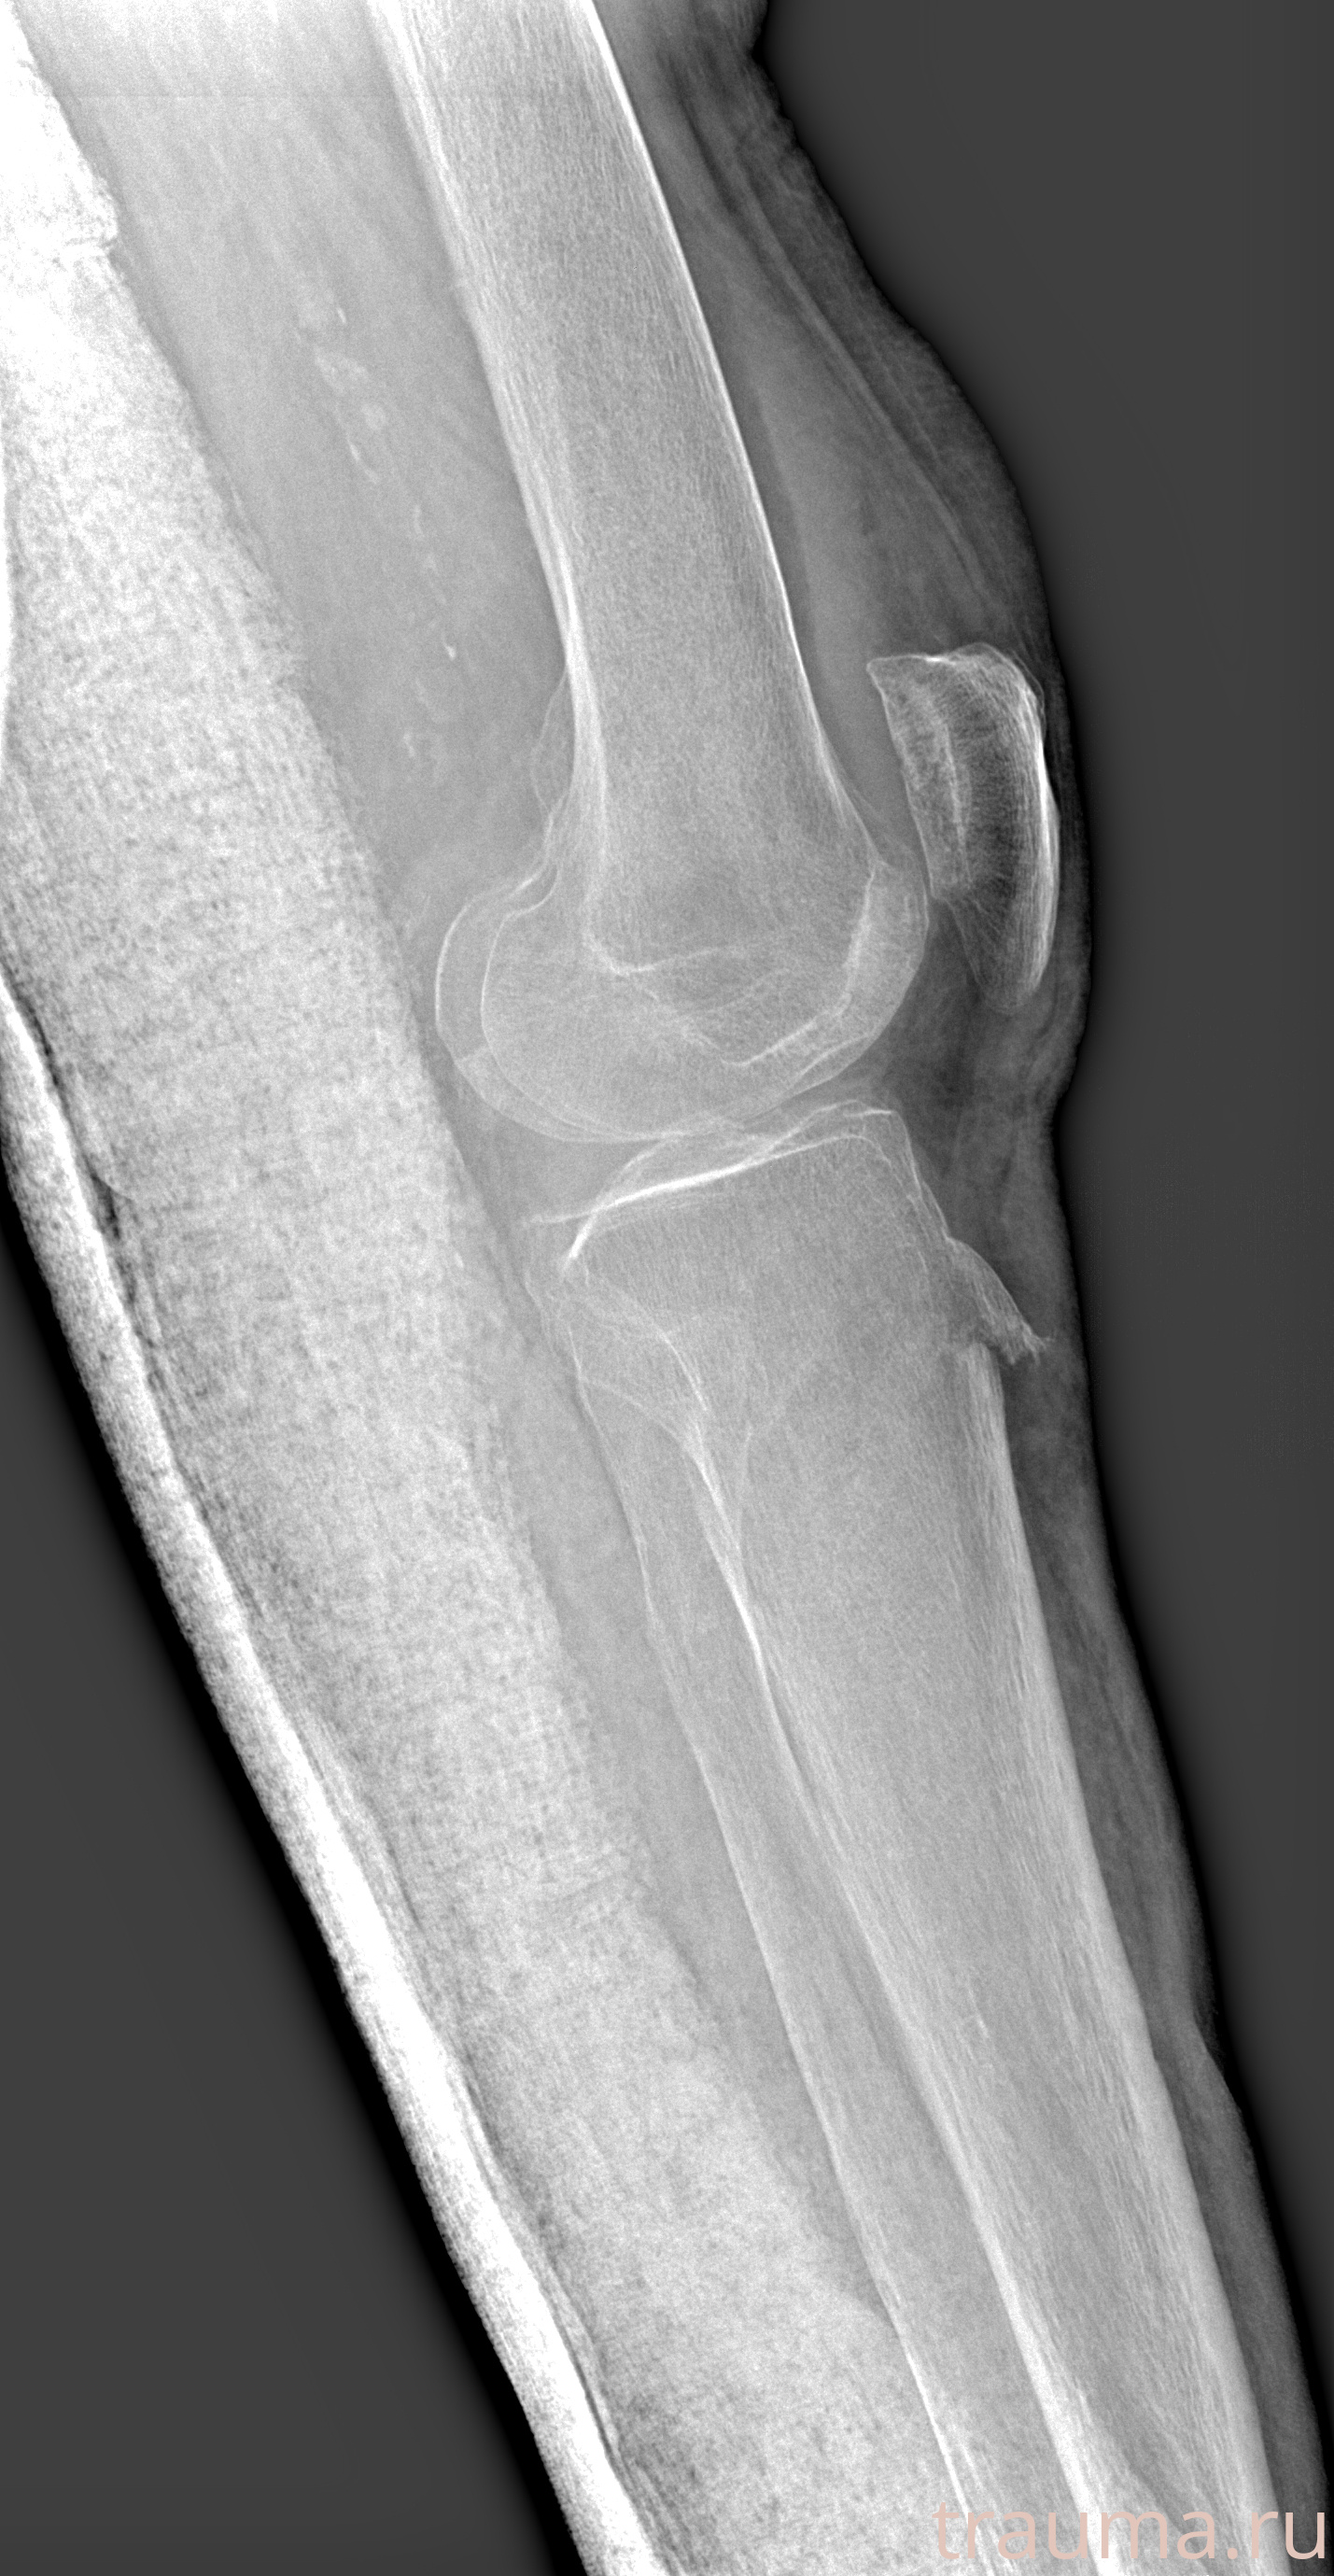

Рентгенограммы

Рентген на дому: по вашему адресу приезжает врач-рентгенолог, травматолог-ортопед с мобильным рентгеновским аппаратом, проводит диагностику травмы или заболевания, делает необходимые рентгенограммы, дает рекомендации по дальнейшему лечению. Получить качественные снимки в домашних условиях возможно благодаря уникальной методике, разработанной МосРентген Центром для института  Склифосовского